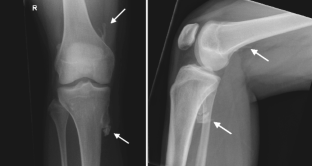

Fibrodysplasia ossificans progressiva (FOP) is a rare genetic disorder and the most disabling condition of heterotopic (extraskeletal) ossification in humans. Extraskeletal bone formation associated with inflammation preceding the osseous conversion usually begins in the first decade, predominantly in the head, neck, and shoulders. All patients have malformed great toes. Most patients have a spontaneous mutation of the ACVR1 gene. We report a 17-year-old girl with malformed great toes who had her first episode of heterotopic ossification and impaired mobility of the left hip at the age of 13 years. No inflammatory fibroproliferative masses preceded the onset of heterotopic ossification. Radiographic studies demonstrated myositis ossificans, but failure to associate the great toe malformation with heterotopic ossification led to a failure to diagnose FOP. She underwent repeated and unnecessary operative procedures to remove a recurrent lesion. FOP was finally suspected when the great toe malformation was correlated with the trauma-induced heterotopic ossification. Genetic analysis confirmed the presence of the classic FOP mutation (ACVR1 c.617G>A; R206H). This case highlights the importance of examining the great toes in anyone with heterotopic ossification. The association of malformations of the great toe with heterotopic ossification in all cases of classic FOP will lead to prompt clinical diagnosis and the prevention of iatrogenic harm.

Fig. 2